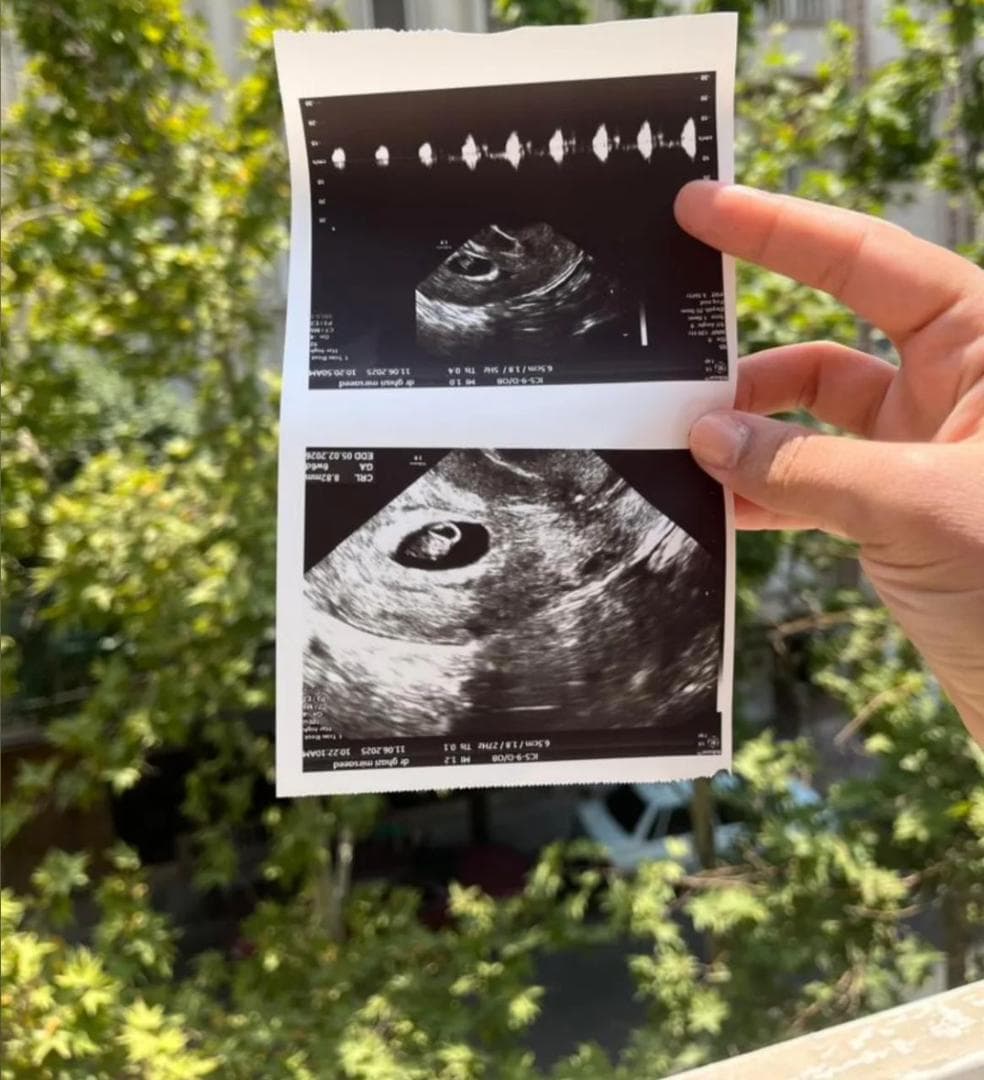

✅ پایشهای دقیق دوران بارداری رحم اجارهای

✅ IVF (لقاح خارج رحمی) با درصد موفقیت بالا

✅ مشاوره ژنتیک و غربالگری قبل از بارداری